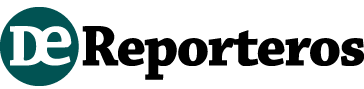

Las arrugas son causadas por el daño crónico solar en la piel, por la mímica facial de cada quien, por falta de humectación, deficiencia alimentaria e incluso por enfermedades como diabetes

Las arrugas son una fragmentación en las fibras elásticas de la dermis. Su nombre científico es ritidosis, dice la dermatóloga Rosa María Ponce Olivera.

Ahí donde hay arrugas, las fibras de la dermis están rotas, la epidermis está adelgazada y los vasos sanguíneos son visibles.

1.-El color o fototipo de la piel: en los prototipos moreno y afroamericano son menos visibles las arrugas, mientras que en los prototipos claros la formación de arrugas es más común.

En el “mundo occidentalizado”, agrega Ponce Olivera, todos quieren ser jóvenes. El estándar ideal es no tener arrugas; fruncir el ceño sin arrugarse y no tener manchas en la piel. Como en las revistas, donde “todas son caras de muñeca”, con piel perfecta, creada por computadora.